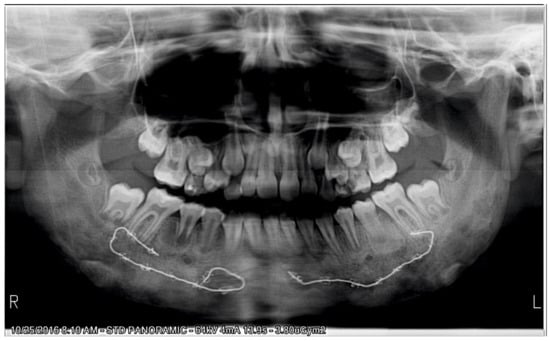

2.3.1. First Treatment Phase—2016—TMJ Splint Therapy

2.3.2. Second Phase of Treatment—2017—Bite-Blocks and Transpalatal Arch